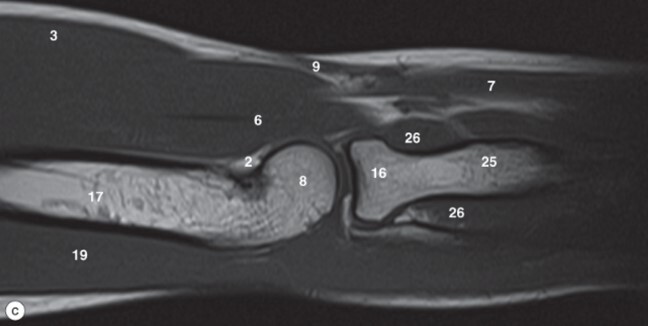

8

Q

Label 1,4,6,16,32,33

A

1-Lt. Basilic vein

4=-Lt. Brachialis muscle

6-Capitulum of Lt. humerus

16=Head of Lt. radius

32-Trochlea of lt. humerus

33= Tuberosity of lt. radius

9

Label 6,16,17,18,22,25,32

6=Capitulum of lt. humerus

17=Lt. Humerus

18=Lateral condyle (lt. humerus)

22=Medial condyle (rt. humerus)

25=Olecranon fossa of lt. humerus

32=Trochlea of lt. humerus

10

Label 19 and 26

19-Lt. Triceps brachii muscle

26-Olecranon process of lt. ulna